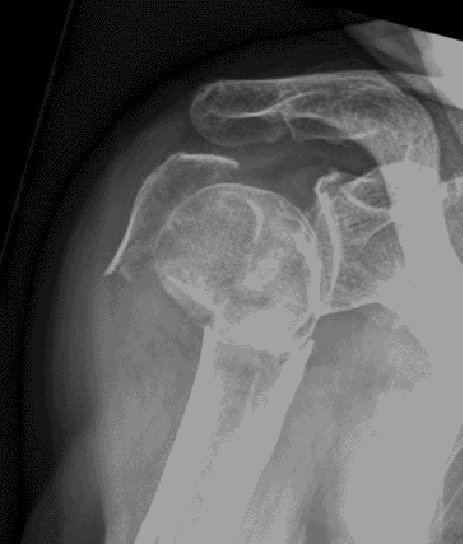

For fracture and revision treatment

The system offers a set of modular Proximal Bodies in several sizes and heights to be paired with a broad range of Modular Stems, available in different diameters and lengths as well as different surface and coating options for cemented and cementless fixation.

The Proximal Bodies’ spiked surface, together with m-l and a-p holes for suture fixation, allow for stable and physiologic tuberosities reattachment. The modular concept of the fracture components supports the surgeon in achieving adequate joint restoration even in cases with poor anatomical landmarks.1